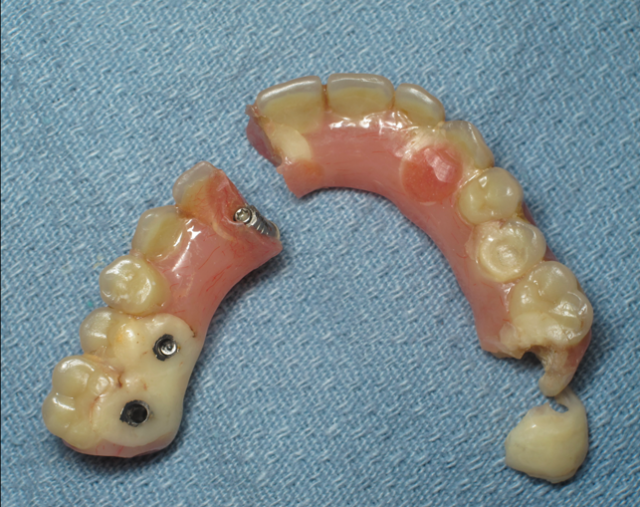

If there is insufficient space, the patient will suffer from a failure of the prosthesis (displaced teeth, fractured provisional, or – rarely – a fractured bar or abutments) or potentially an un-esthetic outcome with the plane of occlusion in the wrong position in the vertical dimension of the face.

I have a dogma: A prosthetic failure of a fixed hybrid is a surgical complication, until proven otherwise. It’s important for the surgical team to accept this responsibility of creating enough space.